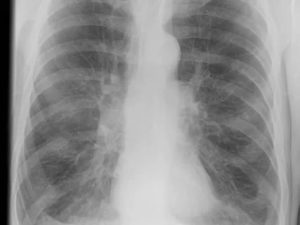

Рентген легких умеренного курильщика мало чем отличается от рентгена легких обычного человека, при условии отсутствия каких-либо патологий.

Флюорограмма представляет собой снимок легких, сердца и окружающих тканей, имеющий неоднородный вид. Это напрямую исходит из принципа проведения любого рентгенологического исследования, заключающегося в неравномерности поглощения органами рентген-излучения.

Если легочная ткань человека находится в нормальном состоянии, то и на пленке (или матрице) она будет выглядеть ровной.

Если в ней происходит воспалительный процесс, картинка будет содержать затемнения разной интенсивности, а участки повышенной воздушности, наоборот, выглядеть высветленными.

Обычно флюорография курильщика выглядит, как обычный снимок без патологий. У заядлых фанатов табакокурения могут быть заметны изменения в легких, что определяется по цвету на фотопленке.

Утверждать с уверенностью, что человек курит, врач по снимку не сможет. У затемнений, которые видны на флюорограмме, есть множество других причин для появления. Поэтому, только взглянув на снимок, однозначно определить наличие пагубной привычки нельзя.

У некурящего человека орган на флюорографическом снимке представлен в светло-серых тонах без затемненных участков. В здоровом состоянии на нем нет ярко выраженных сосудистых линий.

Легочные корни будут прямой формы без признаков воспалительного процесса.

По сравнению с начинающими у курильщиков со стажем структура легких отличается большей плотностью рисунка. На органе врач может увидеть характерную сеточку, при этом зона альвеол будет очернена, а рисунок сосудов проявится четче. Скопления отмерших клеток распознают по характерным темным пятнам на снимке.

Считается, флюорография легких курильщика по виду схожа с показателями людей, проживающих в экологически небезопасных районах.

Изображение здоровых легких выглядит светло-серым, органы имеют четкие границы. Флюорография курящего человека характеризуется появлением “сетки” из альвеол. Чрезмерная выраженность сосудов может свидетельствовать о наличии воспалительного процесса, бронхита, пневмонии. Воспаления в дыхательной системе типичны для людей с никотиновой зависимостью.